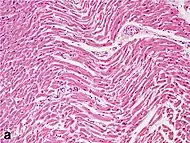

Under the microscope, myocardial infarction presents as a circumscribed area of ischemic, coagulative necrosis (cell death). On gross examination, the infarct is not identifiable within the first 12 hours.[20]

Although earlier changes can be discerned using electron microscopy, one of the earliest changes under a normal microscope are so-called wavy fibers.[21] Subsequently, the myocyte cytoplasm becomes more eosinophilic (pink) and the cells lose their transversal striations, with typical changes and eventually loss of the cell nucleus.[22] The interstitium at the margin of the infarcted area is initially infiltrated with neutrophils, then with lymphocytes and macrophages, who phagocytose ("eat") the myocyte debris. The necrotic area is surrounded and progressively invaded by granulation tissue, which will replace the infarct with a fibrous (collagenous) scar (which are typical steps in wound healing). The interstitial space (the space between cells outside of blood vessels) may be infiltrated with red blood cells.[20]

Differential diagnoses for myocardial fibrosis:

- Interstitial fibrosis, which is nonspecific, having been described in congestive heart failure, hypertension, and normal aging.[25]

- Subepicardial fibrosis, which is associated with non-infarction diagnoses such as myocarditis[26] and non-ischemic cardiomyopathy.[27]

Healthy myocardium versus interstitial fibrosis in dilated cardiomyopathy. Alcian blue stain.

Healthy myocardium versus interstitial fibrosis in dilated cardiomyopathy. Alcian blue stain. Subepicardial fibrosis (epicardium at top)

Subepicardial fibrosis (epicardium at top)